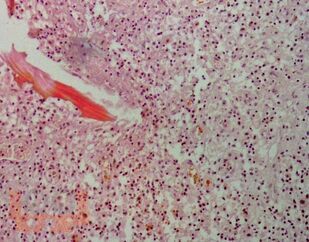

В пособии приводится общее описание одного из патологических состояний костно-суставной системы у детей — небактериального остеомиелита. В общем виде описаны современная теория развития данного заболевания, принципы диагностики и лечения, а также принципиальный тактический алгоритм при небактериальном остеомиелите.